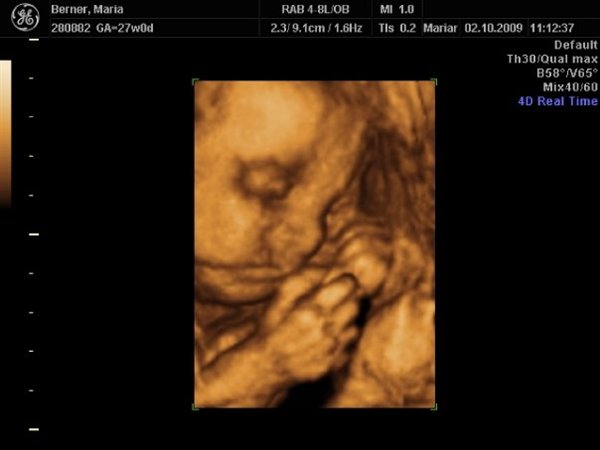

Men vi fik nogle dejlige billeder af Dicte som dog lå og puttede ansigtet ind i livmodervæggen, så det gjorde det lidt svært at få de helt skarpe billeder. Hun var 928 gram, og deres udregning af termin siger også 1. januar

Det er 3. gang nu en scanning har sagt det.